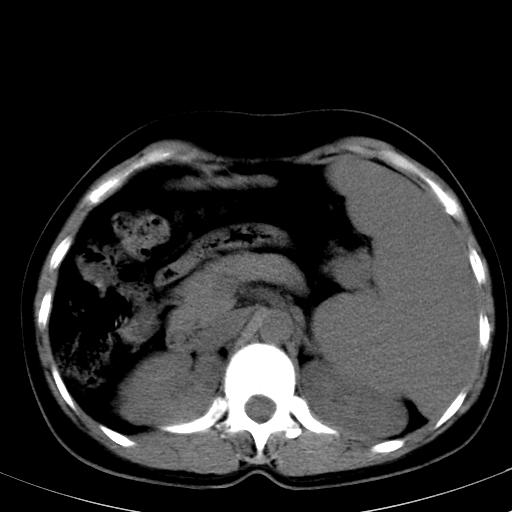

标题: CT19818:女40,脾大伴贫血,无肝炎病史 [打印本页]

标题: CT19818:女40,脾大伴贫血,无肝炎病史

血常规血红蛋白102,

骨穿,诊断再障,无其他病史

脾大符合临床诊断(再障)。

巨脾。

肝硬化、门脉高压、脾大。再障+肝硬化促成巨脾。

肝叶比例失调,肝左叶明显增大,包膜欠规整,脾大,支持考虑肝硬化、门脉高压、脾大。